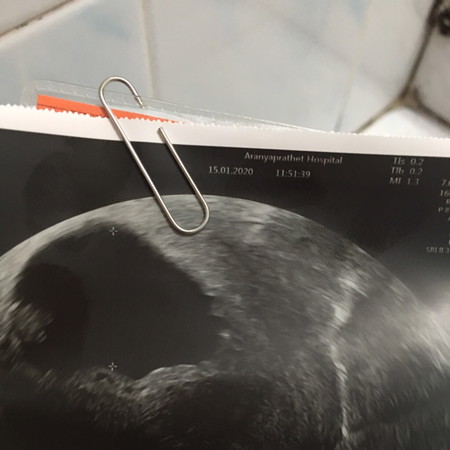

คุณหมอบอกว่าท้องลม หัวใจเด็กหยุดเต้นแล้ว คุณหมอถามว่าจะขุดมดลูกหรือจะปล่อยให้หลุดเอง ถ้าขุดก็เสี่ยงมดลูกทะลุและติดเชื้อได้ง่าย ถ้าปล่อยให้หลุดเองก็ไม่อัตรายแต่ต้องใช้เวลา คุณคิดอย่างไรค่ะ จะขุดหรือปล่อยให้หลุดเอง

เป็นเหมือนกันเลยค่ะคุณแม่ตอนนี้ท้องได้ 10 วีคแล้วไม่พบตัวอ่อนเช่นกันค่ะเพิ่งตรวจวันนี้เหมือนกันค่ะหมอให้ปล่อยเวลา1อาทิตย์ถ้าไม่หลุดต้องไปขูดมดลูกค่ะเพราะถ้าปล่อยไว้นานแล้วไม่หลุดเองจะส่งผลไม่ดีต่อเลือดค่ะ